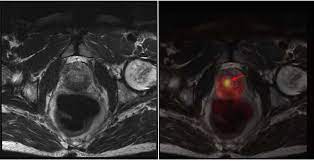

Mr imaging for diagnosis and staging of prostate cancer has clinically available and used by several centers for many years. Mri can not only confirm the presence of prostate cancer but pinpoint its location. An mri can determine whether prostate cancer has … The current diagnostic pathway for prostate cancer has resulted in overdiagnosis and consequent overtreatment as well as underdiagnosis and missed diagnoses in many … Mri is valuable in diagnosing many conditions …

The current diagnostic pathway for prostate cancer has resulted in overdiagnosis and consequent overtreatment as well as underdiagnosis and missed diagnoses in many … Mri scans can show if the cancer has spread outside the prostate … If the scan shows a problem, it can be targeted … Mr imaging for diagnosis and staging of prostate cancer has clinically available and used by several centers for many years. Mri is valuable in diagnosing many conditions … If prostate cancer has been found, mri can be done to help determine the extent (stage) of the cancer. 15.09.2021 · mri a valuable tool in early diagnosis and evaluation of the extent of tumors, such as prostate cancer. If you have a raised psa level, your doctor may refer you to hospital for an mri scan of your prostate.